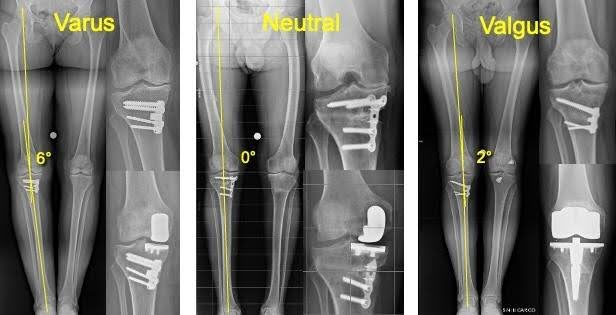

Una precedente osteotomia tibiale (un intervento per correggere l’asse del ginocchio) non è sempre un ostacolo alla protesi monocompartimentale sul lato interno del ginocchio; lo diventa se ha causato una deformazione verso l’esterno del ginocchio (valgo).

Tre tipi di asse meccanico dopo un’osteotomia tibiale alta (HTO): Se l’asse del ginocchio è in varo (ginocchio “a parentesi”) o neutro, si può valutare una protesi monocompartimentale. Se l’asse è in valgo (ginocchio “a X”), è necessaria una protesi totale.